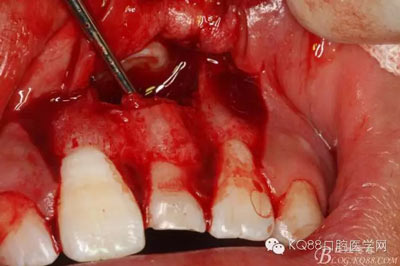

圖17.骨壁重新覆蓋回去

圖18.縫合

圖19.摘除的牙瘤和囊壁組織